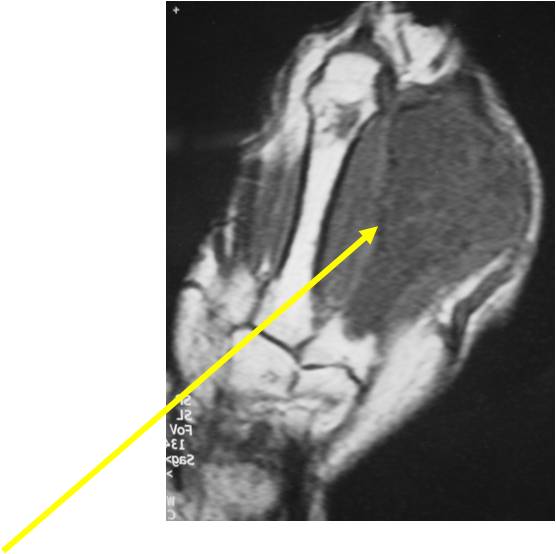

- MRI

- Lobulated margin

- Marked increased intensity long TR images

- Calcified chondroid – low intensity all sequences

MRI:

- Lobulated margin (Lobular Growth Pattern)

- T1 Weighted Images: Intermediate Signal Intensity

- Calcifications will be low signal

- T2 Weighted Images: High Signal Intensity

- High water content shows as high signal on T2 weighted images

- There should never be any cortical destruction nor a soft tissue component. If this exists then the tumor must be a chondrosarcoma.

- Endosteal scalloping and cortical expansion is acceptable for phalangeal tumors. In most benign long bone cartilage tumors there is minimal endosteal scalloping but there should be no cortical expansion nor thickening. There should be no cortical destruction and no soft tissue component associated with an enchondroma. Cortical destruction, periosteal thickening, cortical expansion and a soft tissue component indicates a chondrosarcoma of the long bone.